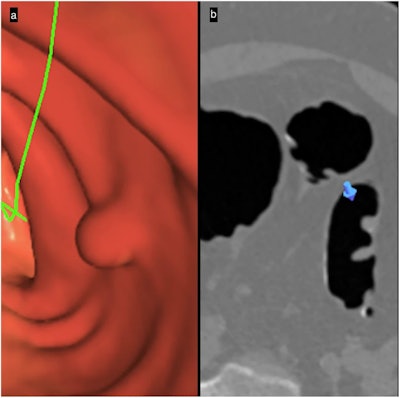

Primary 3D polyp detection: 3D-2D interaction. (a) 3D-endoscopic view makes detecting a candidate sessile polyp easier. (b) The 2D-axial image confirms the polyp’s soft-tissue value, bookmarking on the 2D image (blue arrow) the specific location shown on the 3D image.